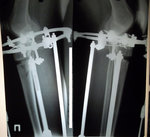

Рентген перед снятием аппаратов.

в аппаратах пред снятием.